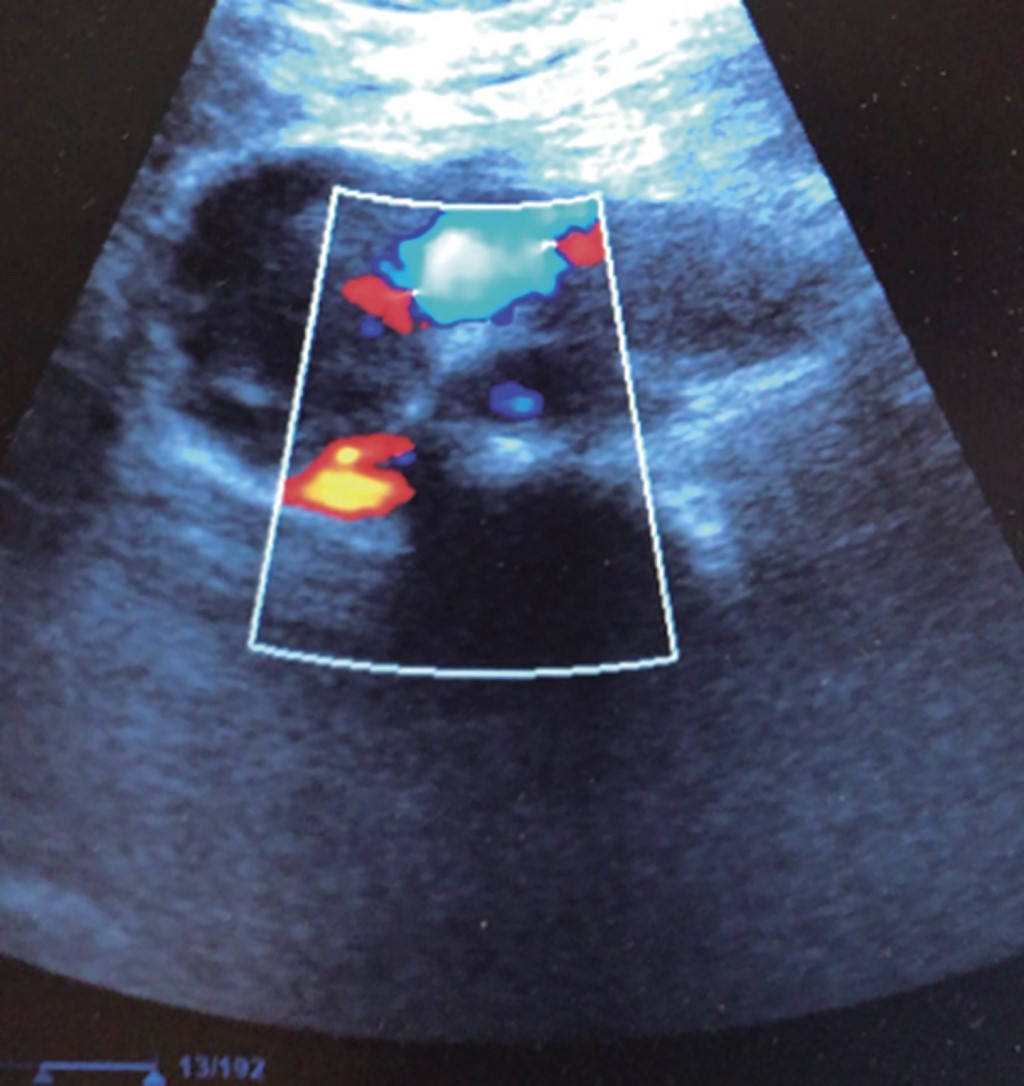

The piezoelectric effect, discovered by Jaques and Pierre Curie in 1881, means that when a certain voltage is applied to quartz crystals, they generate sonic pressure waves that bounce off nearby surfaces and are received as echoes by the crystals. The ability of these crystals to generate and receive pressure waves in the megahertz frequency range enabled the development of modern transducer technology. Every sonographic transducer used in clinical medicine contains such crystals. The emitted sound frequency is too high to be perceived by the human ear. These emitted waves, received as echoes, are sorted by a processor into pixels that generate images amenable to clinical interpretation. In 1820, Jean-Daniel Colladon confirmed that the speed of sound varies according to the medium in which it is dispersed, being slower in an aqueous medium than outside it. Therefore, tissues (or cavities) with different percentages of aqueous density will resist the passage of the sonographic signal (liver, bone, tendon, blood) in a peculiar way. This phenomenon is known as impedance. Finally, it should be remembered Christian A. Doppler's description in 1842 of the effect that bears his name. Imagine an approaching train sounding its horn; when a sound-producing object moves towards an observer, the received sound frequency is higher than the emitted frequency; when the sound producer and the observer are at the same point, the emitted and received frequencies are identical; and when the sound producer moves away from an observer, the received frequency is lower than the emitted frequency. The equipment equipped with the color Doppler reproduces this phenomenon by translating images of moving fluids (circulating blood), either approaching (red color) or moving away (blue color) from the transducer (those interested in the history and fundamentals of the physics of ultrasound can consult this interesting document).10 The ultrasound machine consists of two main parts, the transducer and the processor (although some novel portable ultrasounds contain the processor inside the transducer). It is sufficient to connect them to a tablet or smartphone with the brand's application, which functions as the screen or monitor of the device used (Figure 1). The transducer has two main functions: first, to generate a high-frequency sound wave (it acts as an emitter) and, second, to receive a reflected sound wave (it acts as a receiver of the echo that the emitted wave generated). The processor inside the ultrasound unit takes these incoming signals and converts them into a useful image. The tissue impedance alters the emitted waves, that is, the resistance that the tissues oppose to the passage of the sonographic signal; the greater the impedance, the greater the bounce of the signal, or what is the same, the greater the echogenicity. A hard structure (a stone, bone) completely resists the passage of the signal; it bounces and generates a bright white image (hyperechoic image) (the bone or the litho where the signal hit), followed by a dark shadow, i.e., the so-called posterior acoustic shadow (where the signal did not reach at all, hence the darkness). On the contrary, soft tissues (tendon, muscle, liver, kidney, thyroid, intestinal wall, some tumors) each oppose their own varieties of impedance, generating images in gray contrast without acoustic shadow that are translated in each of them in a characteristic sonographic image, as for example the contrast that has the echogenicity between renal cortex and medulla.11-13 A liquid object surrounded by a soft tissue wall (gallbladder, a cyst, a blood vessel) allows the signal to pass through freely, generating a dark (anechoic) image, surrounded by the wall that is seen in white and persists in the lower part of the screen, a phenomenon characteristic of the low impedance of liquid media known as "posterior enhancement". Organs or structures composed of soft tissue such as the liver and the kidney, or a tumor mass, which are close neighbors or continents of blood vessels, reproduce an ultrasonographic signal that clearly shows the parenchyma and the vessel (portal vein, renal vessels, inferior vena cava, supra-hepatic veins, bile ducts, collecting system). With the addition of color Doppler, within a solid mass (liver, tumor), it can be confirmed that it is crossed by a pulsatile blood vessel, and all these structures can be measured in terms of diameter, volume, pulsation, and so on. A gallbladder occupied by stones will show white (hyperechoic) images inside the gallbladder, which, by being hard, generate a hyperechoic (white) contour image and cast a posterior acoustic shadow. The abdominal wall, constituted by soft tissues with different impedances, allows differentiating muscle, tendons, aponeurosis, fat, and strange phenomena such as a solution of continuity with the emergence in the Valsalva maneuver of a soft tissue, which translates into the objective diagnosis of a wall hernia. Pathological collections (blood, pus, serous fluid) can be identified, such as an anechoic band between the liver and the right kidney (Morrison's space), corresponding to intraperitoneal blood or free fluid. Current ultrasound equipment is manufactured with such technical refinement that it allows a remarkable resolution, facilitating the exploration of any tissue, be it tendon, joint spaces, muscle, eyeball, or thoracic, pericardial, or abdominal cavities, and the images generated can be measured, photographed or videotaped in real-time. It is possible to share these findings via the internet in seconds. Who can believe this tool should not be in the hands of the clinician who seeks objective, concrete, measurable, and immediate answers? Other ultrasound principles that affect our imaging, including absorption, scattering, and angle of reflection, are beyond the scope of this article but can be consulted in the referenced articles.14

The general surgeon deals with clinical problems involving the digestive tract, the neck, the abdominal wall, and disorders of the circulatory system and the thorax. A paper published in 2008 by Lindelius,15 demonstrated that the implementation of ultrasound by the general surgeon in cases of acute abdominal pain increased diagnostic accuracy by 7.9%. In the daily consultation of the specialty, incorporating sonographic scanning to the explored area adds minutes to the clinical examination that provides data of notable value due to its objectivity and precision. The abdomen is usually the site most frequently explored by general surgeons. It is possible in a daily consultation to do the entire upper abdominal ultrasound protocol in minutes, which includes both upper quadrants and the flanks, being able to observe the liver, gallbladder and bile ducts, both kidneys, the spleen, part of the pancreas and, with the help of color Doppler, the main vessels of the region such as the inferior vena cava, abdominal aorta, portal vein, splenic vessels, and the hepatic artery. There may be limiting factors such as gastric contents, the filling level of the gallbladder, or the patient's constitution and ability to cooperate with the study. However, with daily practice, sufficient skills and refinement are acquired to achieve, with accumulated experience, images of immediate diagnostic relevance. In the training phase, contrasting our findings with information available on the web, with imaging colleagues, or surgeons already experienced in ultrasound, will allow the essential feedback and mentoring of any learning curve. Traditionally, it was considered that those organs containing a mixture of liquid and gas (intestine, stomach) are not assessable by ultrasound; the gas produces a rarefaction effect, as it does not compress the waves as a solid tissue or a liquid medium, the signals are then scattered preventing them from returning as echoes and allowing the processor to form an image congruent with the scanned organ. However, when this condition changes due to a pathological state, it is possible to identify the intestinal or gastric contents and give us a more approximate idea of what is happening in that abdomen. We can, for example, tell whether a stomach is full of liquid or whether the intestine contains solid, liquid, or gaseous residue. Today's equipment can even see the intestinal wall in detail when it is dilated. It can be distinguished when the colon is fluid-occupied at the level of the left flank as might be in amebic colitis or intestinal occlusion,16 where dilatation of the small bowel ≥ 25 mm, abnormal peristalsis, the presence of free intraperitoneal fluid and edema of the bowel wall are seen (Figure 2). In cases of acute abdominal pain, ultrasound can immediately allow differential diagnoses, such as the finding of a pyelocaliceal dilatation due to nephrolithiasis (Figure 3) or an abdominal aortic aneurysm (Figure 4). A prospective study performed in Irvine, California,17 found that the diagnostic ability of the first contact physician performing ultrasound to detect cholelithiasis has a specificity of 87% and a sensitivity of 82%, while the ultrasonography test performed by an imaging physician had a sensitivity of 83% and a specificity of 86%. In other words, by saving the patient's time, the diagnosis of cholelithiasis is feasible by adding a few minutes to the initial physical examination. In cases of appendicitis, the diagnostic method considered the gold standard is computed tomography (CT). However, it has drawbacks, such as its availability, its cost, and the risk of radiation in children and pregnant patients. In such situations, especially in children, females, or thin patients, ultrasound is a powerful tool that complements the initial clinical examination. The advantages of ultrasound over CT are its ubiquity (it is already in the emergency room), low cost, absence of radiation, and differential diagnosis with gynecologic or genitourinary causes of pain. In appendicitis, the sensitivity and specificity of CT are 99.4% and 80.0%, respectively. For ultrasound, the diagnostic sensitivity is 83% and specificity is 90%. The rate of negative appendectomy is slightly higher in the CT group than in the ultrasound group, i.e., 7.1% (3/42) (CT) compared to 4.67% (5/107) (ultrasound). It should be emphasized that ultrasound is an operator-dependent technique. Experience and quality of the equipment play an important role.18 Appendicitis has several characteristic findings, such as an edematous wall and general thickening. A noncompressible non-peristaltic tubular structure measuring more than 6 mm in diameter in the right lower quadrant is taken for criteria of positivity (Figure 5).19-21